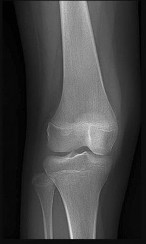

Figures 5a and 5b are the radiographs of a 74-year-old man with poorly differentiated squamous cell carcinoma of the lung. He has had an uneventful recovery after undergoing a wedge resection of his left upper lobe 6 months ago. He is experiencing left lateral knee pain, and a whole-body positron emission tomography/CT scan shows no avid area other than the lateral left distal femur. This patient has needed to use a wheelchair for 3 weeks because of his pain. You discuss these treatment options: aggressive curettage, local adjuvant treatment, cementation, and prophylactic fixation vs distal femoral resection and megaprosthesis total knee arthroplasty reconstruction. You should tell him that

Distal femoral megaprosthetic reconstruction after tumor resection is a reliable oncologic procedure, but 5-year implant survival is as low as 74% with an approximate 8% deep infection rate. The amputation rate is as high as 8% because of infection or recurrence, and there is an overall 18% revision rate. More than 10% of distal femoral megaprosthetic reconstructions are performed to address metastatic disease.

Fixation failure and infection may occur with either procedure. Radiation may not be recommended after a megaprosthesis reconstruction unless margins are not free of tumor. Either operation may be equally successful in returning patients to functional activities. Overall disease-free survival is related to the aggressiveness of the tumor and not the type of reconstruction performed.